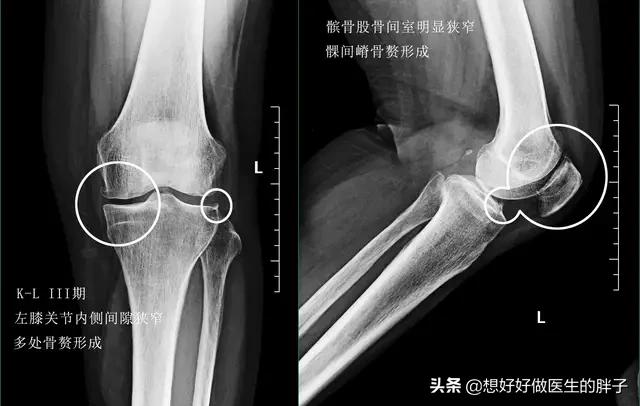

●骨关节炎的中期:当骨关节炎发展到中期的时候,在x线上患者的骨关节间隙就会有狭窄了,骨赘也会明显的增多。很多患者此时关节已经开始出现了轻度的畸形,患者的症状往往也会比早期的时候明显的加重,行走一个小时左右或者更短的时间,就会出现明显的关节疼痛,而不仅仅表现在上下楼梯时关节疼痛,这些患者会出现关节内的积液。这些症状以及x线表现,往往代表着患者关节内的软骨已经磨损的比较严重了。